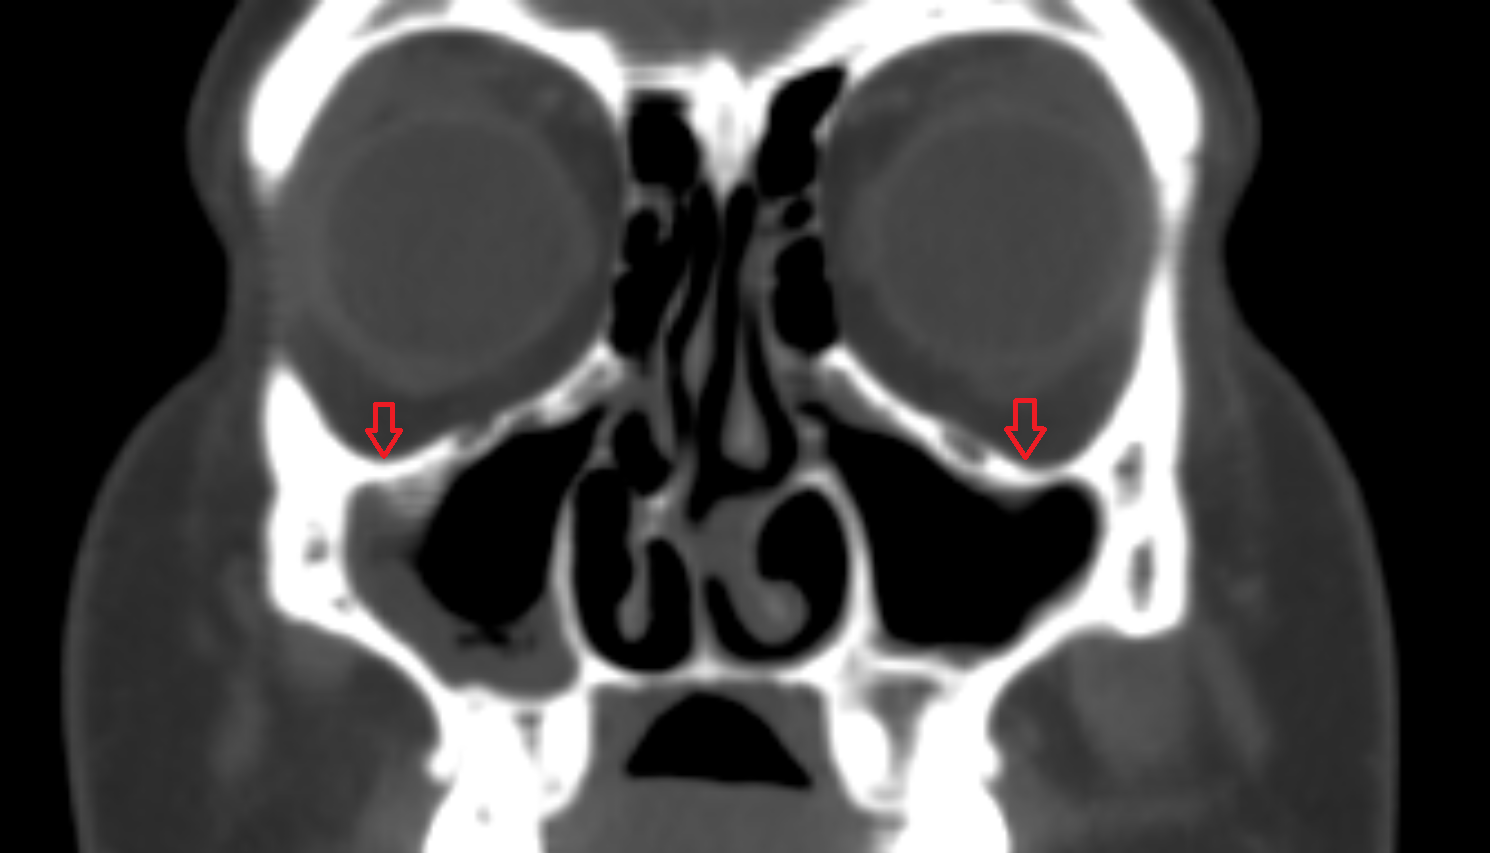

- Maxillary sinus